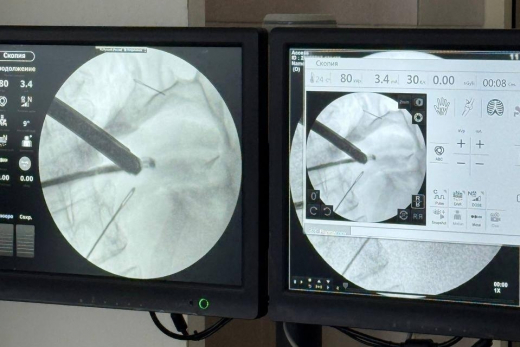

В Подмосковье врачи спасли женщину, которая наглоталась швейных иголок. Об этом сообщает Telegram-канал Министерства здравоохранения Московской области. Пациентка обратилась в Красногорскую больницу с жалобами на боли в животе. Во время диагностики у нее обнаружили три иглы в брюшной полости и одну — в передней брюшной стенке. Одна из них прошла через стенку желудка и даже проникла в поджелудочную железу. Выяснилось, что женщина проглотила иглы почти месяц назад. За это время они успели обрасти тканями. Сперва врачи планировали извлечь инородные предметы с помощью лапароскопии, через небольшие проколы. Однако из-за возникшего кровотечения хирургам пришлось экстренно перейти на полноценную операцию с рассечением брюшной полости. В результате врачи даже сумели сохранить пронзенную железу. Ранее в департаменте здравоохранения Москвы рассказали , какие необычные предметы приходилось извлекать из пациентов столичным врачам. «Топ-10 предметов: сосиска, семечка, рыбная кость, нож, батарейка, гелиевый шар, монета, арахис, иголка и... 38 магнитов единоразово», — перечислили в депздраве.